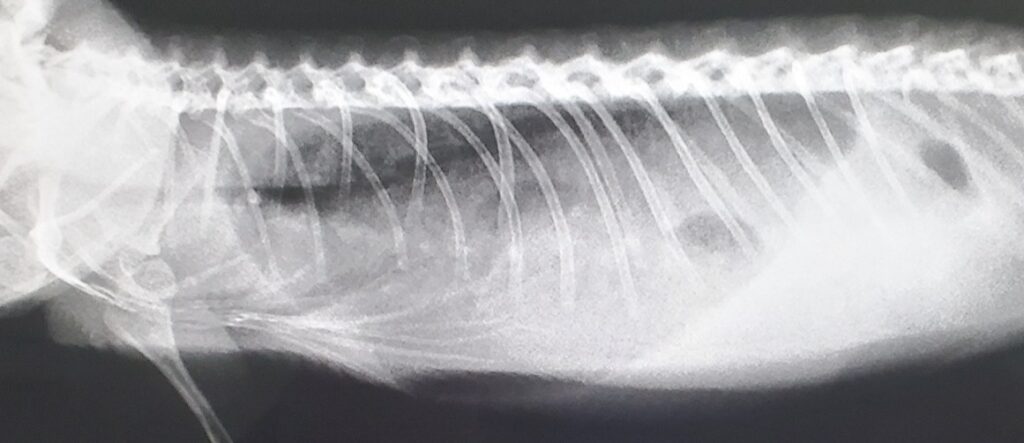

肺炎の確定診断には、 X線検査が必要です。X線所見の解釈肺炎の所見として、肺野における不透過性の増加が認められます。これらの所見は、炎症性の細胞浸潤や滲出液の貯留を示唆します。また、占拠性病変による肺の圧迫がないかも評価されます。